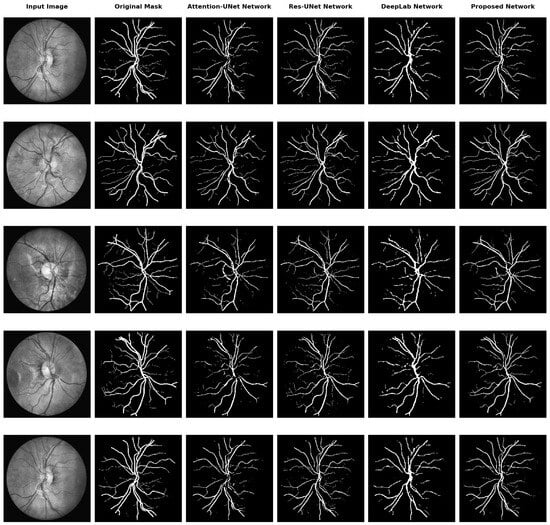

Additionally, we conducted a visual comparison of segmentation results obtained from different baseline models and our proposed model. Figure 3 illustrates the segmentation outputs for five different input retinal images from the CHASEDB1 dataset. Meanwhile, Figure 4 illustrates the segmentation outputs for two different images from the ISO-STAR, HRF, and LES-AV datasets. The results from Attention U-Net, ResU-Net, DeepLabv3+, and our proposed model are compared side by side.

Significant variations in vascular connection and continuity across the various baseline models can be seen upon visual evaluation of the segmentation data. For example, DeepLab has poor vessel-to-vessel connection, leading to discontinuous and fragmented vessel segments. This is explained by the DeepLab architecture’s intrinsic constraints in capturing the contextual data and long-range dependencies required to keep vessels connected.

Even while vessel connectedness is better than in DeepLab, as demonstrated by the segmentation results from Attention U-Net, ResU-Net, and our suggested model, there are still some vessel fractures and discontinuities. Obstacles like vessel overlap, low contrast areas, or noisy image artifacts can cause these gaps and compromise the precision of segmentation algorithms.

Figure 3. Qualitative analysis of the proposed network and its comparison with existing segmentation baseline models.